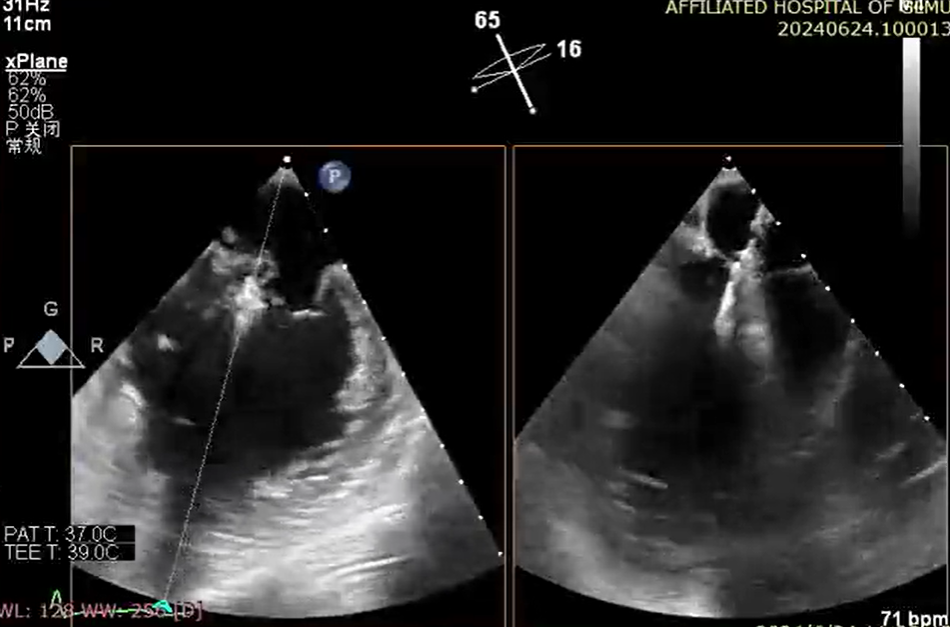

6 月 24 日,心血管内科一病区廖发荣、何武金团队在中山大学附属第一医院庄晓东教授的指导下,在患者右侧腹股沟区穿刺一个 3-5 毫米的小创口,然后将器械通过股静脉穿刺房间隔,把「二尖瓣夹系统」送入患者左心房,进而到达心脏的二尖瓣口,然后全程在食道三维超声引导下,精准夹合二尖瓣后瓣病变区域。

钳夹后,二尖瓣反流从术前 4+改善至 1+、夹合稳定、平均跨瓣压差 2 mmHg,患者术后心功能得到明显改善,无相关并发症,于 6 月 29 日顺利出院。7 月 12 日,患者到医院复查各项生理指标基本正常。